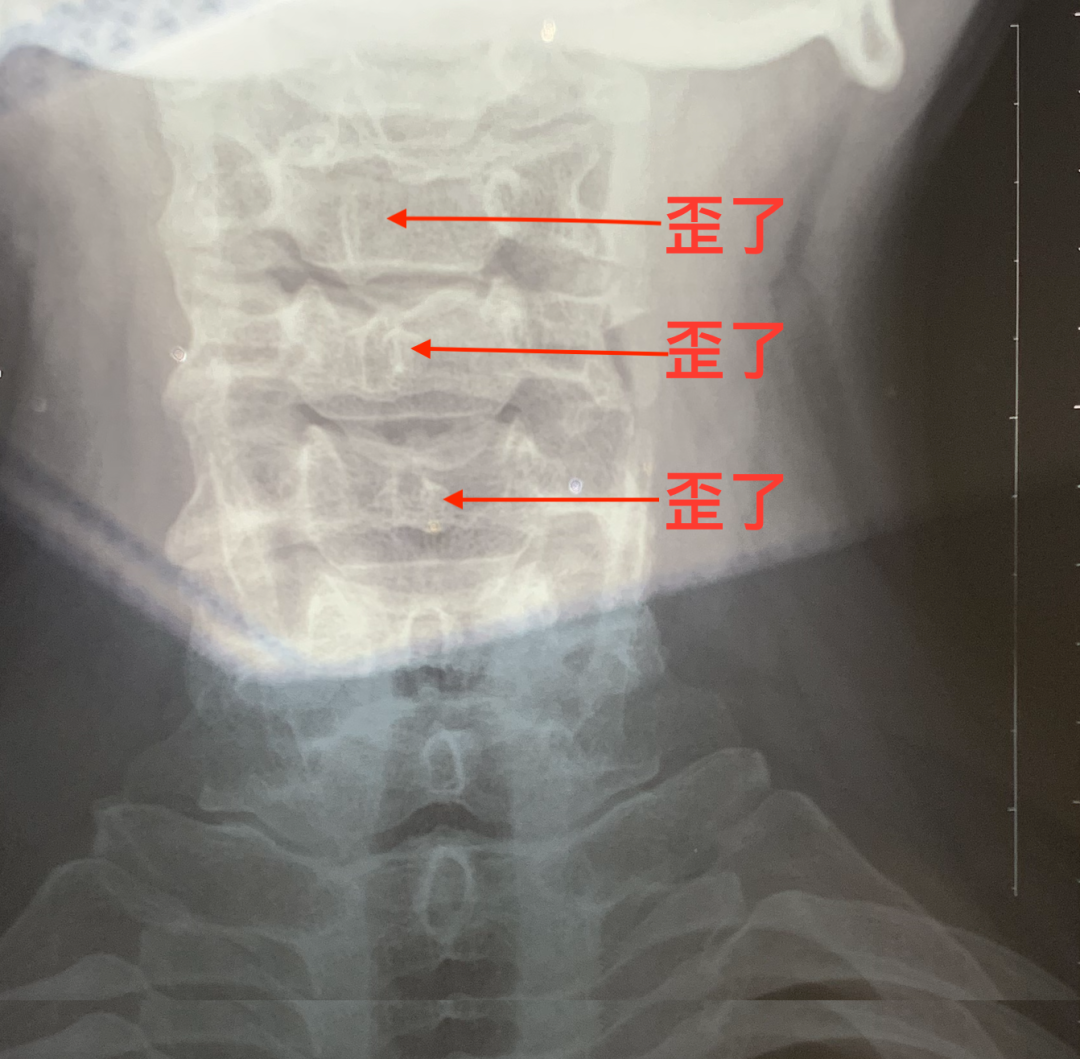

医生说,我长期久坐在电脑前写作,颈椎关节有三节已经歪了,下面是我的X光图:

朋友们看到了吗?我有三节颈椎关节,已经歪了、移位了。